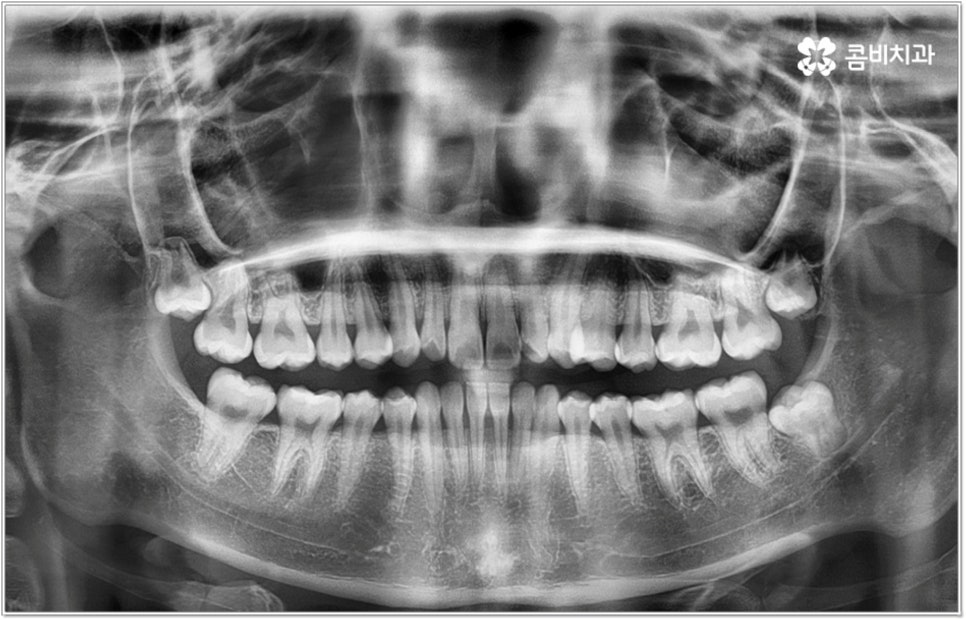

무리하지 않고 돌출입치아교정 과정을 진행하기 위해서는 먼저 꼼꼼한 검진 및 분석에 따른 철저한 맞춤 치료 계획 수립이 중요하다고 할 수 있는데요. 특히 3D CT 및 모르페우스 시스템을 통해 현재 아이의 치열이나 연조직, 상하악 관계 등을 자세히 살펴보고 안모 분석 후 교정 치료가 끝난 예상 모습을 시뮬레이션해서 보여주면 환아의 흥미를 유발하고 앞으로 진행될 사항에 대한 이해도를 높여줄 수 있어 긍정적인 영향을 줄 수 있으니 정밀 검진 장비를 갖추고 숙련된 의료진이 치료하는 치과에서 돌출입치아교정 과정을 진행하시길 권유드리고 있어요.

돌출입치아교정 치료에 있어서 방법이나 기간 등 자세한 사항은 환자분들에 따라 달라지는데 다른 문제 없이 치아의 각도만 앞으로 뻐드러진 경우에는 비교적 빠르고 간편하게 개선이 가능한 반면 부정교합 정도가 많이 심각하거나 골격적인 원인이 굳어진 경우 외과적 악교정수술이 병행 돼야 할 수도 있는 만큼 말씀드린 것처럼 제때 검진부터 꼼꼼하게 받아보시길 권유드리고 있습니다.